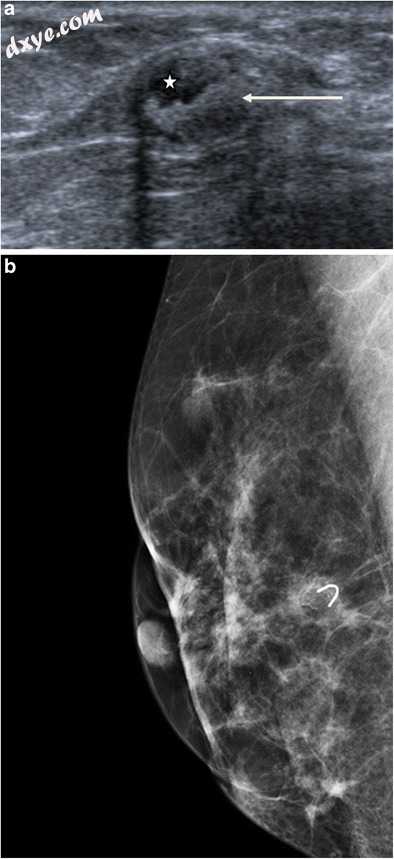

错构瘤

错构瘤是一种无痛,可移动的肿块,由不同比例的腺体,脂肪和结缔组织组成。乳房X线照相术可视化包含射线可透过的脂肪区的边界良好的椭圆形肿块,与对应于纤维组织的密集区域交替,由清晰的假包膜包围。超声波显示出一个界限清晰的椭圆形可压缩物质,周围环绕着细小的​​光环。错构瘤倾向于低回声,等回声或混合,但有时可能具有高回声外观,这取决于各种成分的比例。大约12-43%的错构瘤可能出现高回声[6,13]。可以观察到声学阴影,声学阴影和衰减的混合,或边缘效应伪影(图7a和b)。

图7

错构瘤。 超声显示椭圆形肿块,具有混合回声,全球等回声,具有边缘效应假象。 b乳房X线照相显示边界清晰,致密,椭圆形肿块,外观略微不均匀,与其混合含量(脂肪和基质)有关